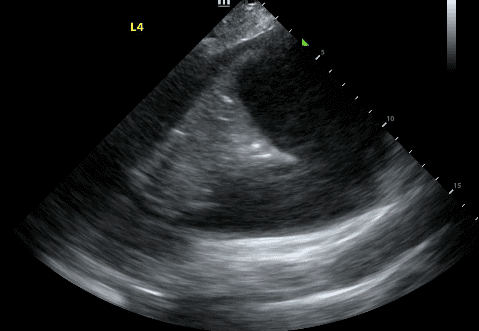

Next, identify the patient’s liver (if your probe is on the right side) or spleen (if your probe is on the left side). Above that, you will see a thin, hyperechoic line which is the patient’s diaphragm.

Finally, above the diaphragm, you will see one one of two things: if there are normal lungs without a pleural effusion, you will see an aerated lung obscuring the diaphragm during inspiration. This is referred to as a “curtain sign.”

If a pleural effusion is present, there will be an anechoic (ie. black) space above the diaphragm. Please note that an anechoic space below the diaphragm represents ascites; not a pleural effusion. Two other other features will stand out to you. Firstly, you will see a “spine sign.” Normally, the spine cannot be visualized above the diaphragm since aerated lung scatters ultrasound beams before it can reach the spine. However, a pleural effusion will allow sound waves to be transmitted to the spine and you will see the spine clearly visible above the diaphragm.